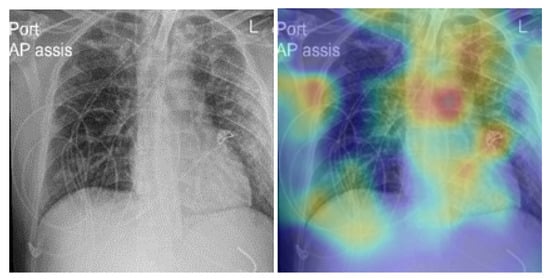

5. Model Explainability